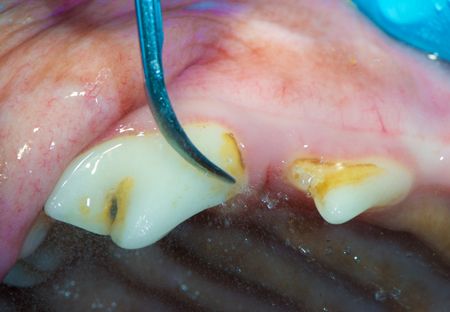

Despite the discoloration, Gus has the first-and easiest to fix and prevent-stage of periodontal disease: gingivitis. Specifically, she has marginal gingivitis secondary to plaque-covered calculus.

Periodontal disease starts with plaque. Daily plaque biofilm accumulates on the teeth, especially over the maxillary cheek teeth, which are bathed with saliva. If the biofilm is left undisturbed, minerals in saliva convert the plaque to rough calculus, attracting more plaque, which inflames the gingiva in many dogs and cats.

In this case, ultrasonic scaling was used to remove the plaque and calculus.